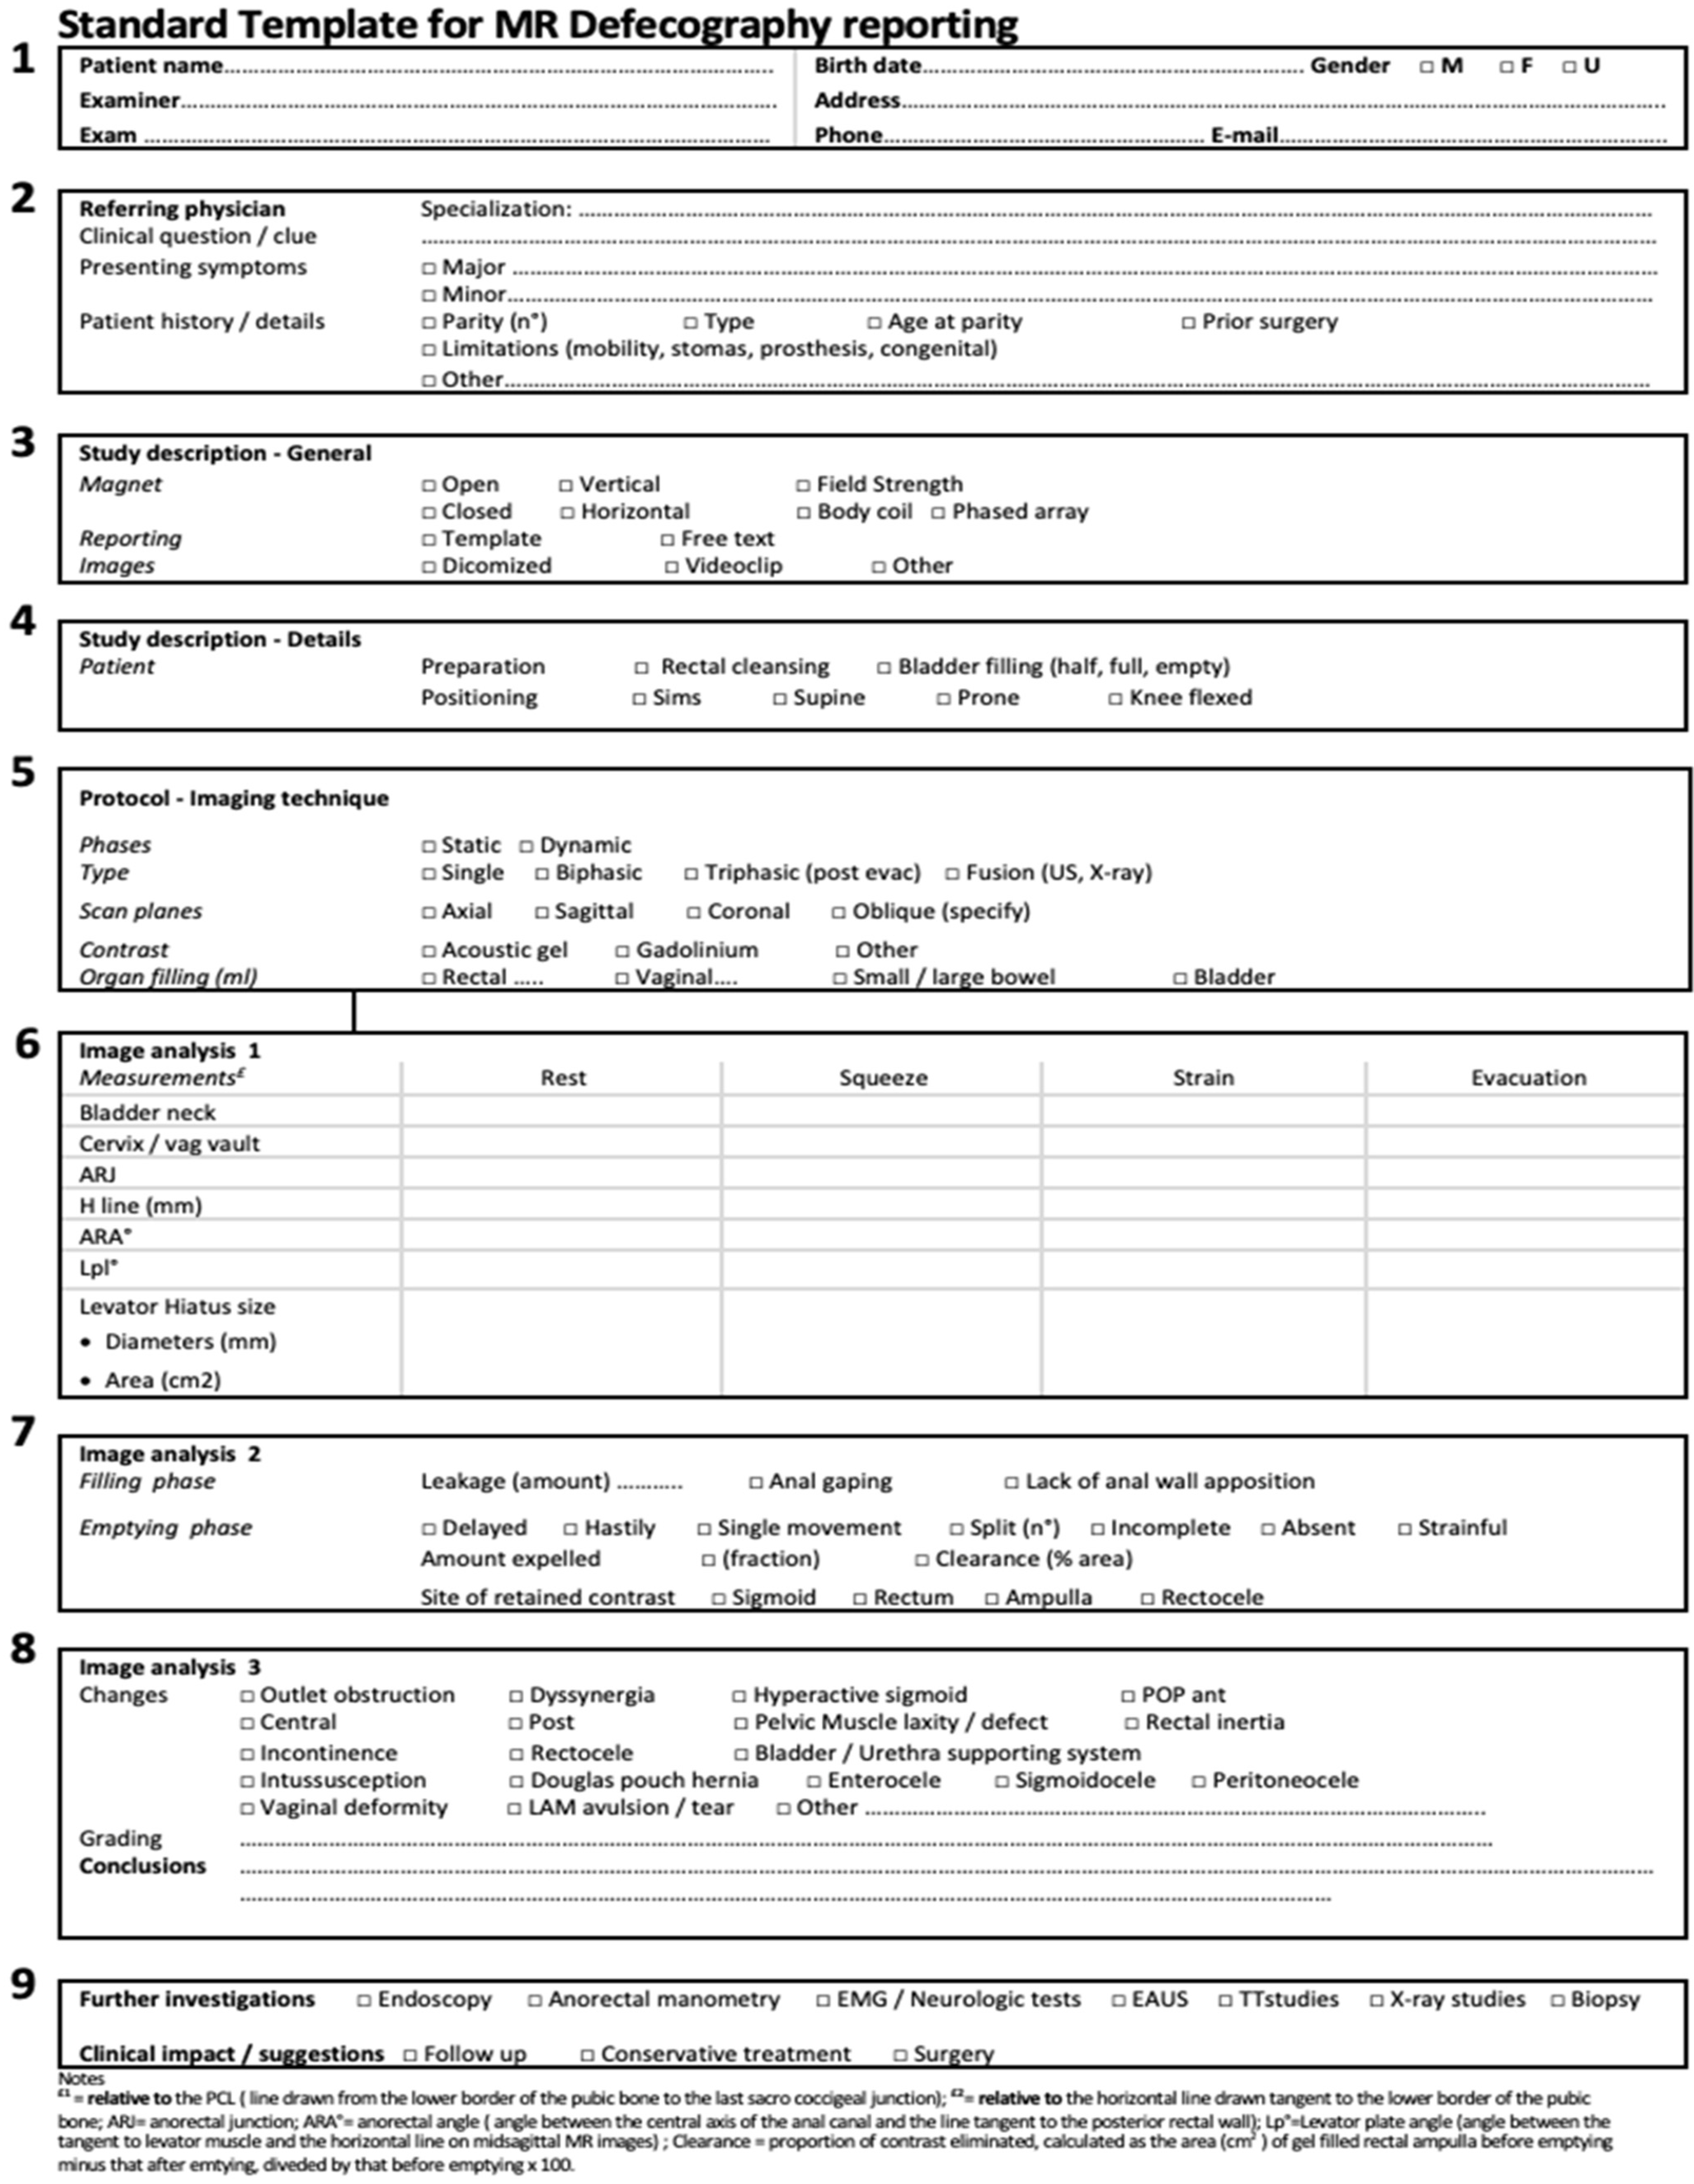

6. The Proposed MR Template